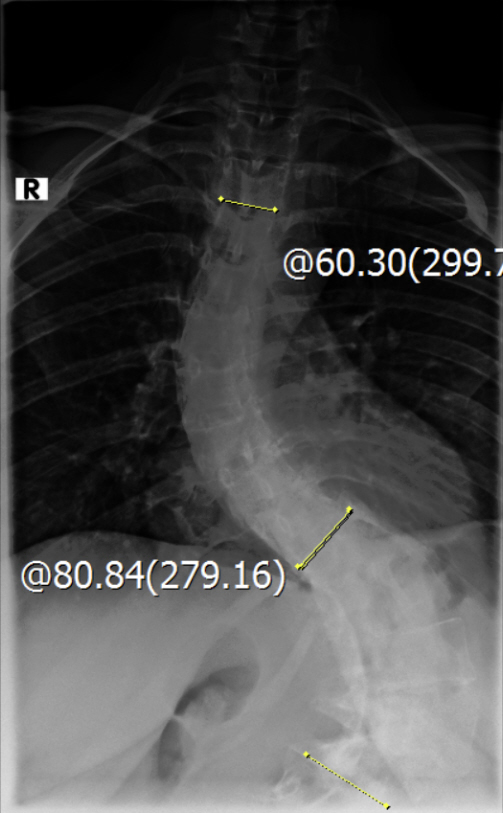

Diagnose: Thorakolumbalskoliose - Cobb-Winkel 60 und 80

Thorakolumbalskoliose mit aktuellen COBB-Winkeln von 80 und 60 Grad...wenig Schmerzen und daher meistens glücklich :D .

Viele kennen sich aus, daher möchte ich euch meine aktuellen Röntgenbilder nicht vorenthalten und hänge sie unten an.

Ich war beim MVZ Gersthofen, dort wurden die Röntgenbilder gemacht…die massive Verschlechterung war sehr offensichtlich :( , drum wurde ich gleich an die Experten zur Hessing Klinik überwiesen.

Dort wurden die Winkel gemessen, unten 80 Grad und oben 60 Grad…eine Verschlechterung von über 2 Grad pro Jahr, wenn man es auf die ganze Zeit berechnet :( .

Die Winkel hab ich nachgemessen, wie der Arzt der Hessing und hier mal als Screenshot

2021-09-09_messung_winkel_1oben.jpg

(115.98 KiB) Noch nie heruntergeladen

2021-09-09_messung_winkel_beide.jpg

(127.19 KiB) Noch nie heruntergeladen